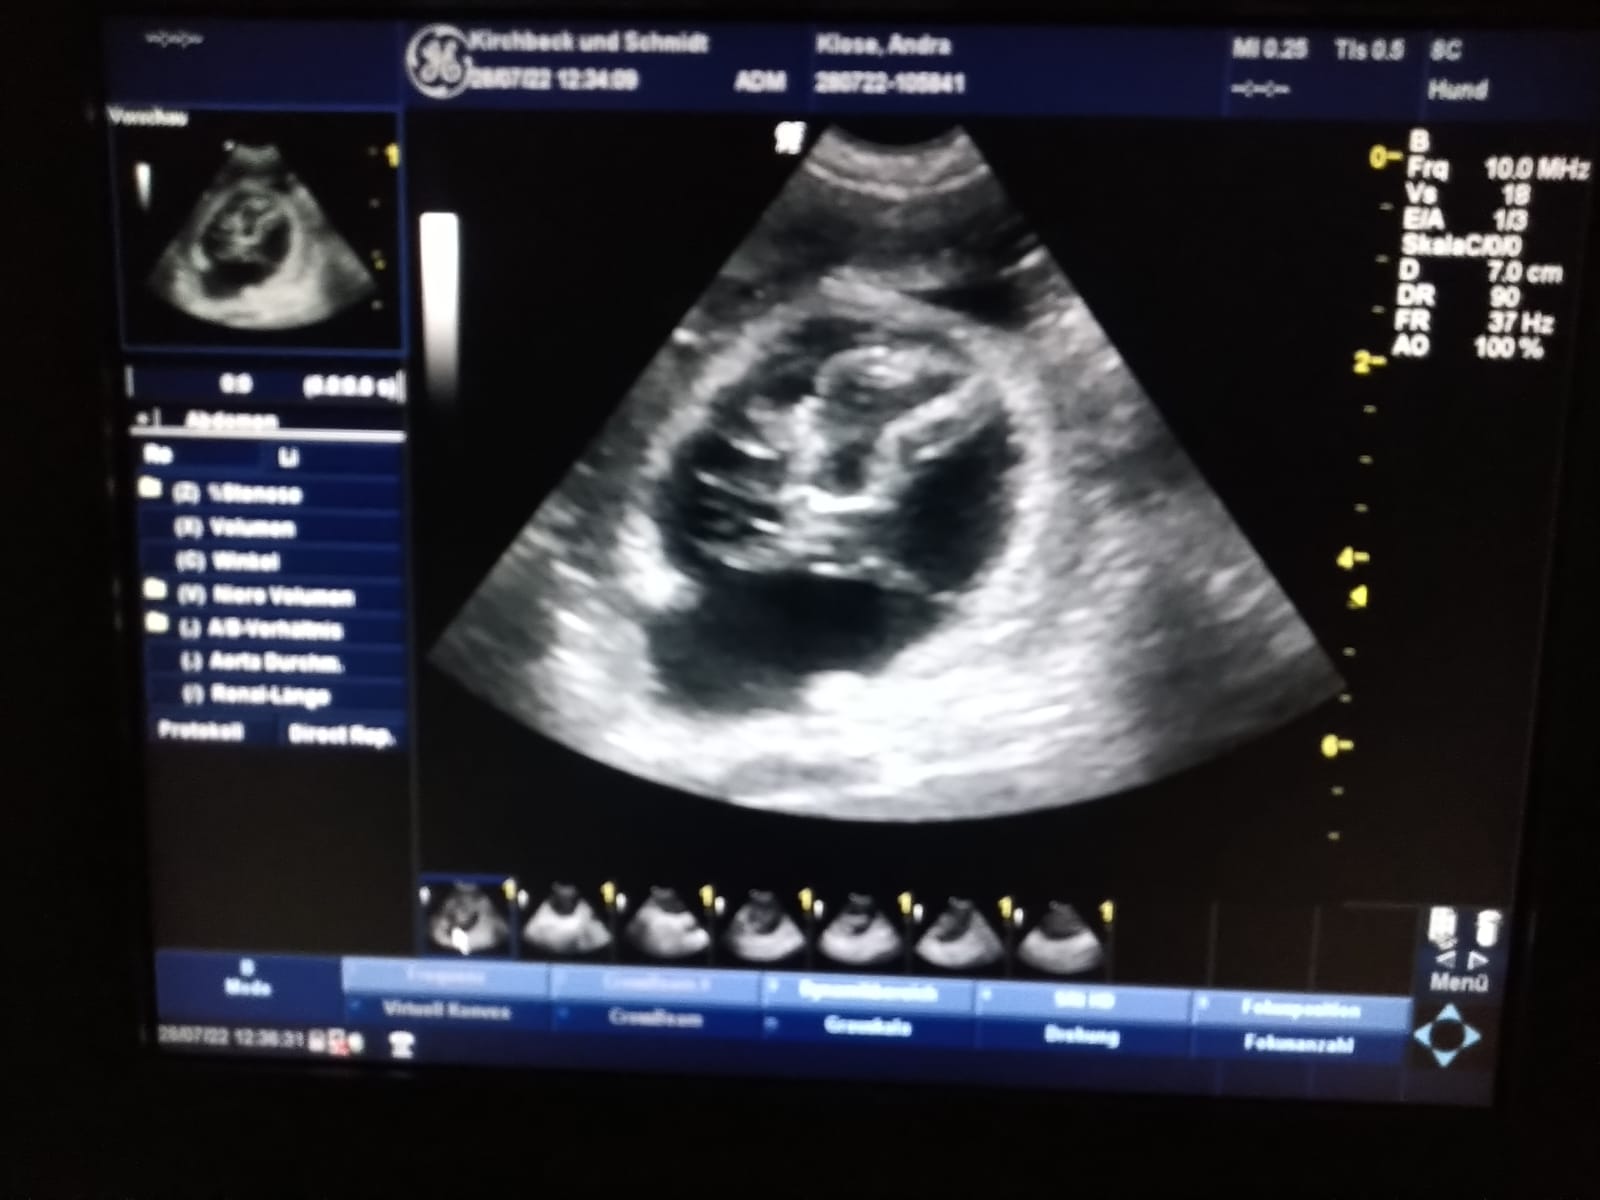

Caspien Awedante und Andra vom Dinkelhook warten auf Nachwuchs...

Wir hoffen auf Welpen in allen drei Farbschlägen. Ende Juli, nach dem Ultraschall wissen wir mehr und auf der C-Wurf-Seite

werden wir weiter berichten!